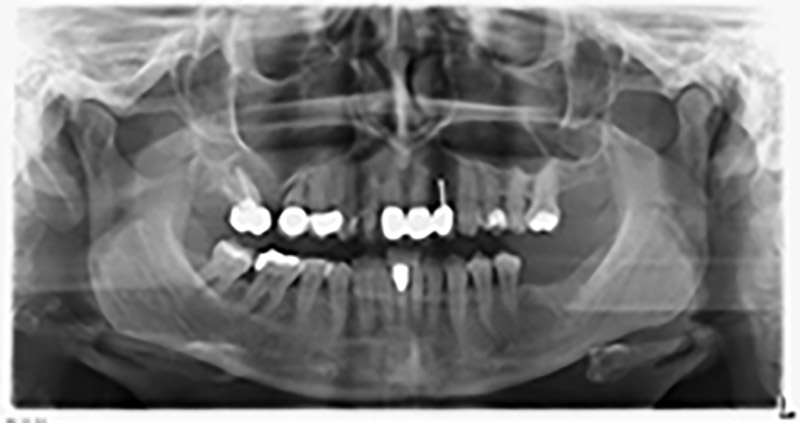

The 59-year-old patient presented with an advanced case of periodontitis, describing an unpleasant feeling and poor taste from the first quadrant in a distal direction. The clinical examination revealed generally enlarged periodontal pockets and very advanced bone atrophy in regions 16 and 14. The radiology confirmed the findings (Fig. 1). Teeth 16 and 14 could not be retained.

Image 1: Orthopantomogram with bone atrophy in region 16–14. *